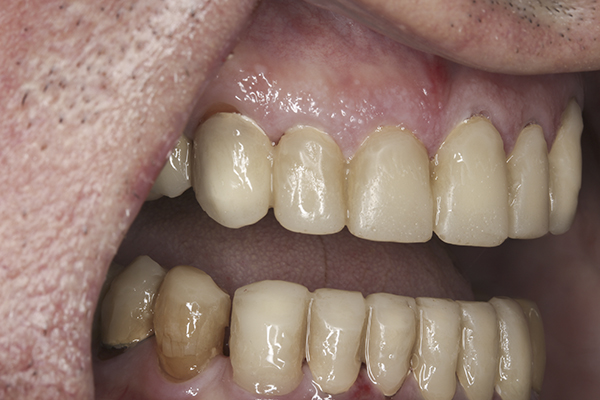

(9.) Preoperative right lateral, closed view.

Figure 9

(10.) Preoperative anterior, closed view. Note the end-to-end occlusion of the anterior teeth and the wear on the incisors and centrals resulting in no anterior or canine guidance.

Figure 10